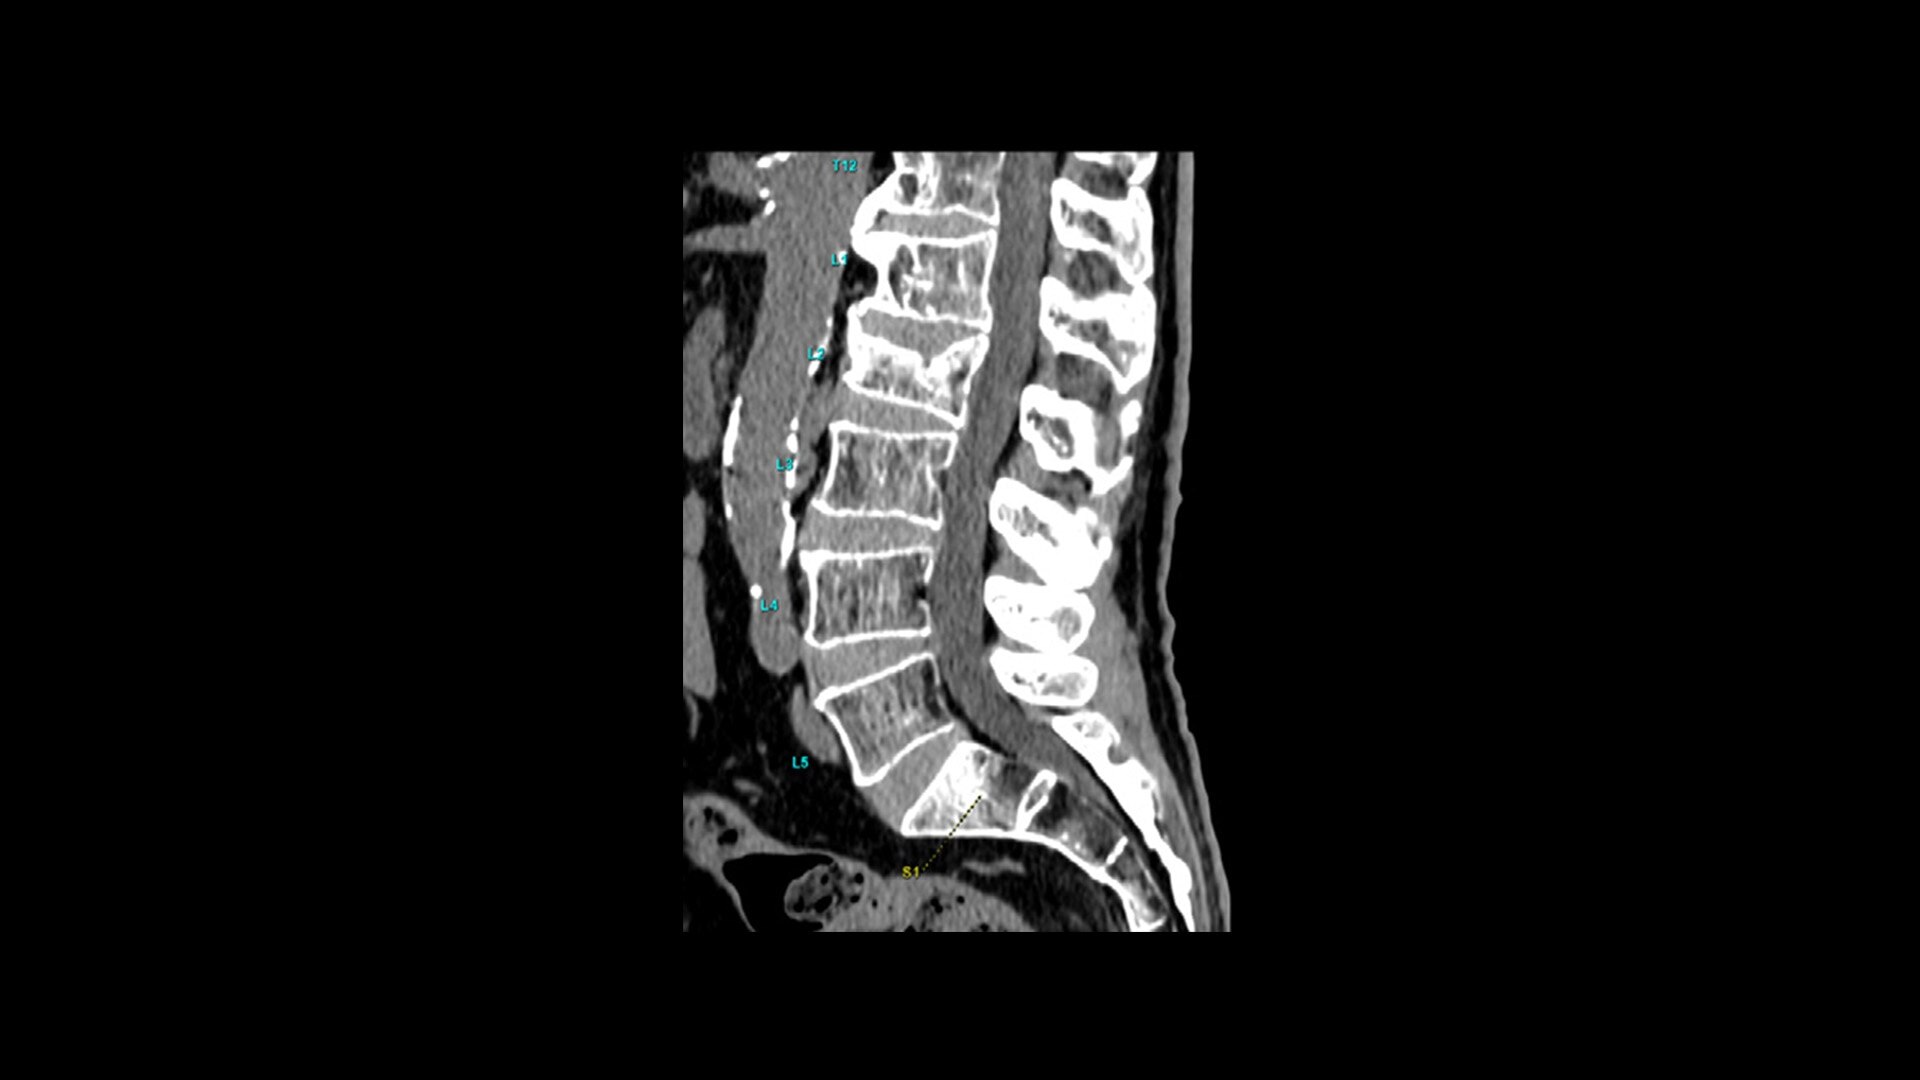

Effortless Workflow

Simplified scanning from start to finish

Available on all Revolution Ascend Platform configurations, Effortless Workflow intelligently automates your CT workflow from pre-scan protocoling to post-scan processing. It uses AI-based features to help transform the entire CT experience and provides maximum efficiency, accuracy, clarity and consistency.

This enables technologists to automatically and accurately personalize scans for each patient with significantly less effort. The end result is a beautiful CT image acquired in less time.